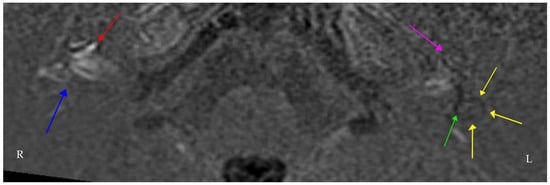

| Subtle left-beating nystagmus on left gaze only Bilateral catch up saccades in the horizontal plane on clinical head thrust testing (bilateral loss of vestibular function). Positive Romberg test Ataxic gait Normal positional (Dix-Hallpike) testing Summary: bilateral vestibular impairment, more marked on the right. Evidence of impaired dynamic and static balance. | Pure tone audiogram: bilateral moderate-to-severe SNHL, worse on the left Vestibular testing: Video head impulse test: bilateral low gain in both horizontal and vertical canals, with prominent covert and overt catch-up saccades on horizontal canal testing Impulsive rotational testing; minimal nystagmus generated bilaterally. Summary: bilateral audiovestibular dysfunction with hearing marginally worse on the left and vestibulopathy worse on the right. | Contrast-enhanced MRI four hours after IV Gadolinium: right cochlea enhancement, bilateral cochlear and vestibular hydrops and additional hydrops in the left lateral semicircular canal. |

| Clinical Examination | Audiovestibular Testing | Imaging |

| No spontaneous- or gaze-evoked nystagmus, normal saccades and normal smooth pursuit. Bilateral catch-up saccades in the horizontal plane, more obvious on the right on head thrust testing. Positive Romberg test Ataxic gait–marked Impaired tandem gait Positional (Dix-Hallpike) testing: normal Remaining neurological examination–normal apart from global peripheral hyporeflexia. Summary: bilateral vestibular impairment, more so on the left. Evidence of impaired dynamic and static balance. | Pure tone audiogram: bilateral profound SNHL Otoacoustic emissions: bilaterally absent Acoustic reflexes: bilaterally absent Vestibular testing–video head impulse test: bilateral low gain in both horizontal and vertical canals, more so on the right, with prominent covert catch-up saccades on horizontal canal testing on the right Summary: bilateral, largely symmetric, audiovestibular dysfunction. | Contrast-enhanced MRI IAMs and brain: bilateral cochlear enhancement and enhancement of the vestibule, lateral semicircular canal and cochlear nerve on the left. Pre-contrast T1 shortening suggestive of Cogan’s syndrome but differentials include inflammatory conditions (sarcoid, connective tissue disease, Behçet’s disease), infection and CSF-borne spread of neoplastic disease. CT temporal bones: nil significant findings |